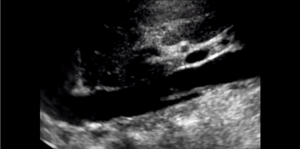

A deep vein thrombosis, DVT, is a blood clot in the veins. It is one of the presentations of venous thromboembolism. The other is, of course, pulmonary embolism. A DVT can occur in the veins of the upper or lower extremity. They can also occur in the deep veins of the abdomen. Technically, it can…